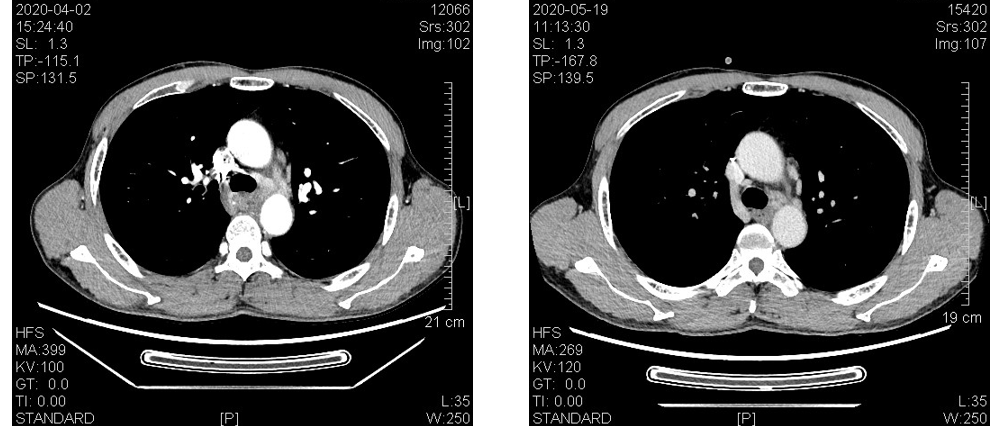

疗效对比(左:4月2日CT结果,右:5月19日CT结果):

食管CT(基线)示:胸中下段食管壁不规则增厚形成肿块,增强后见强化,最厚处约为1.7cm,长约13.4cm,上抵T4水平,下达T9下缘水平,病变段食管与降主动脉间的脂肪间隙消失,与其周长的接触面约为三分之一,向前压迫心包后缘,向左前紧贴左主支气管后壁,后壁略弧形受压改变,向右与奇静脉间的境界不清。

纵隔各大血管结构清晰,上纵隔食管旁、主动脉弓旁、主肺动脉窗、隆突下及后纵隔食管左旁见多发淋巴结,大者截面积1.1cm*1.2cm。

2020年4月2日钡透示:胸中段食管管腔狭窄,长约10cm,局部管壁僵硬,边缘及粘膜不规则破坏,对比剂通过缓慢,其上方管腔扩张明显。